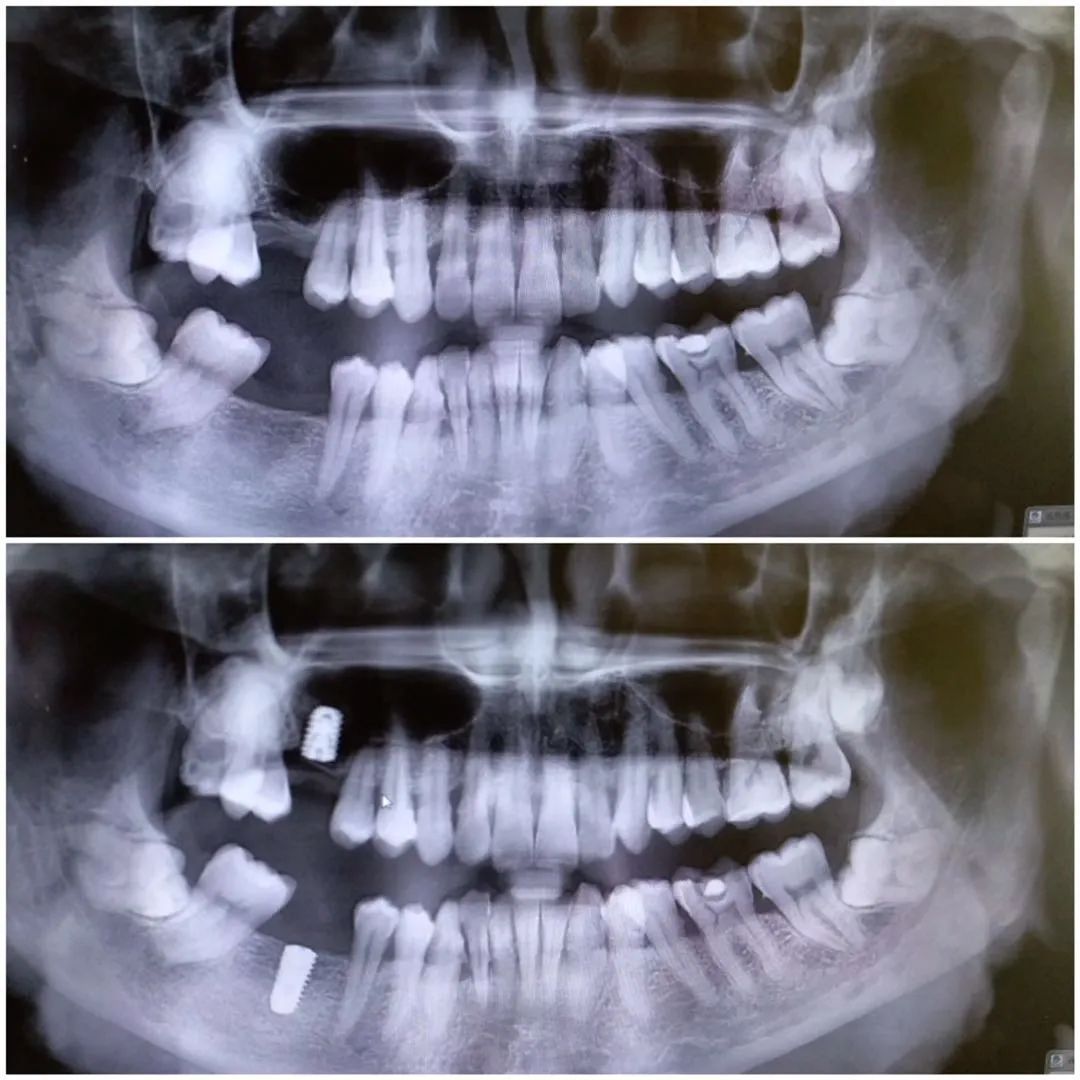

40多岁大叔,种植牙修复。